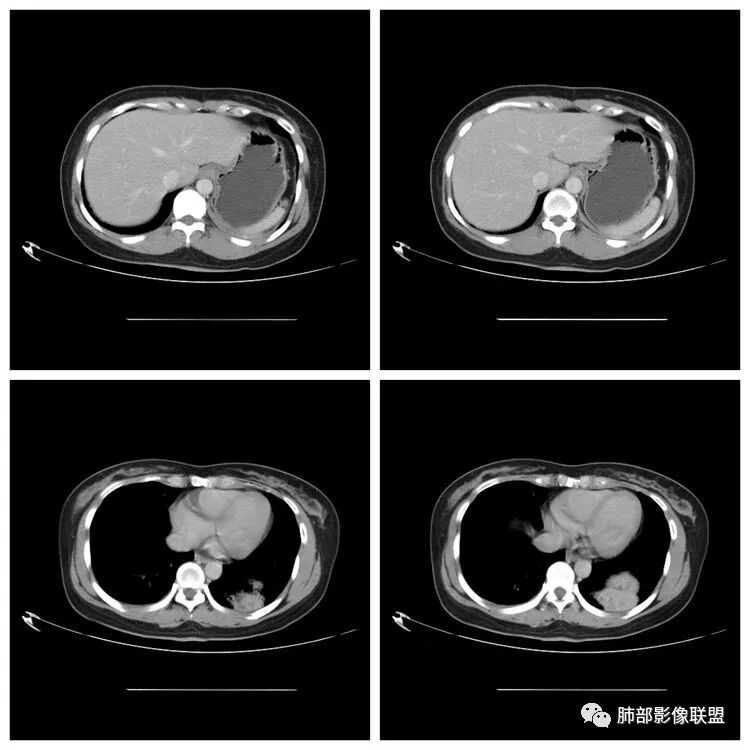

下面看第三部分了,3月20日补增强扫描:

M-Imaging :错了,这么大,膈肌后方南边:定位?定性?Shelia:肺外。感觉病灶是个扁平状,虽然没有蛇纹血管征,但是延迟强化,怀疑纤维来源,考虑sft

M-Imaging :肿块与胸膜夹角是锐角,有分叶,觉得肺内Lotus:mpr重建再看一下南边:与支气管有关系吗Shelia:没有关系。与胸膜分不清

南边:

宇宙星空:没有关系。长轴与胸膜平行吧?

Coke with ice:与肺韧带有关系。与肺韧带的夹角呈钝角,感觉有胸膜尾

宇宙星空:糊墙关系:

南边:边缘这么光滑,无分叶,与胸膜关系密切

D字征

首先良性,倾向于SFT,不除外PSP

小微:肺外肿瘤

宇宙星空:延迟明显强化,其内可见条索状低密度,支持SFT

lmg:其内可见血管穿行吧,考虑SFT

一米阳光:与膈胸膜关系密切,肺受压。考虑SFT

远方: